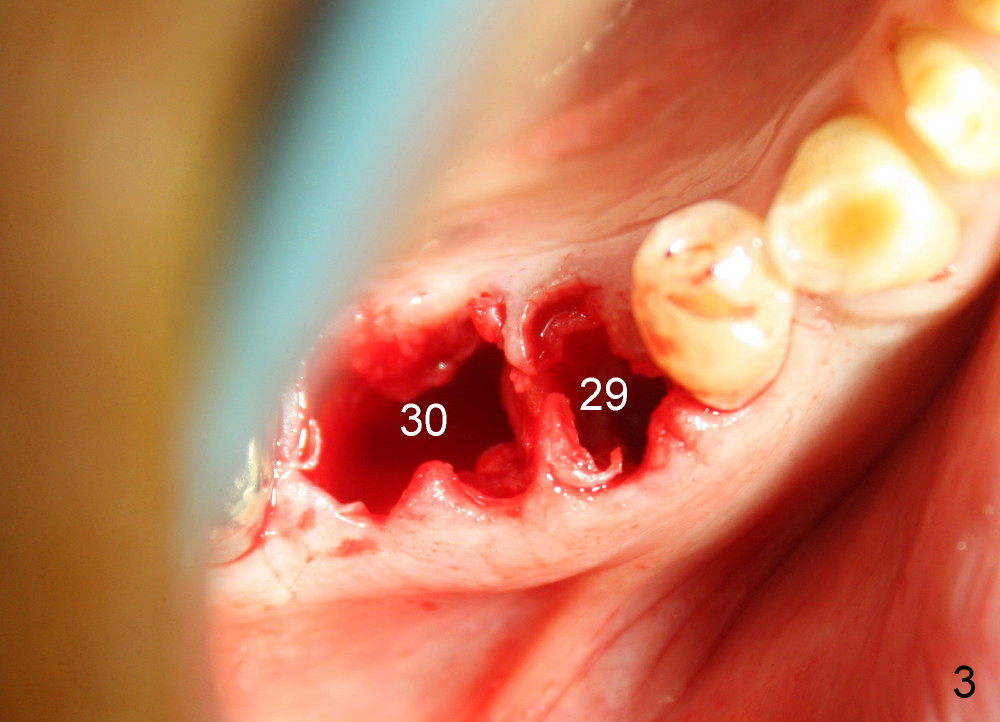

A 84-year-old man has broken the lower right 2nd bicuspid (Fig.1: #29). It is scheduled to be extracted and have an immediate implant. When the residual root is removed, the apical distal wall is too painful to be debrided. Intraop PA shows a perforation (Fig.2 between arrowheads) between the bicuspid and the 1st molar. There is large radiolucency around the mesial root of the molar. A closer look demonstrates a fistula buccal to the molar (Fig.1 <). It appears that the molar is nonsalvageable and should be replaced by an immediate implant. Due to schedule conflict, it is decided to do socket preservation first. Fig.3 reveals that the tooth #30 is extracted. Both of the sockets have been thoroughly debrided and ready for bone graft (allograft and Osteogen). The coronal portion of the bone between these teeth has undergone green stick fracture during molar extraction. Note that the buccolingual (B-L) width of these two teeth is almost identical.